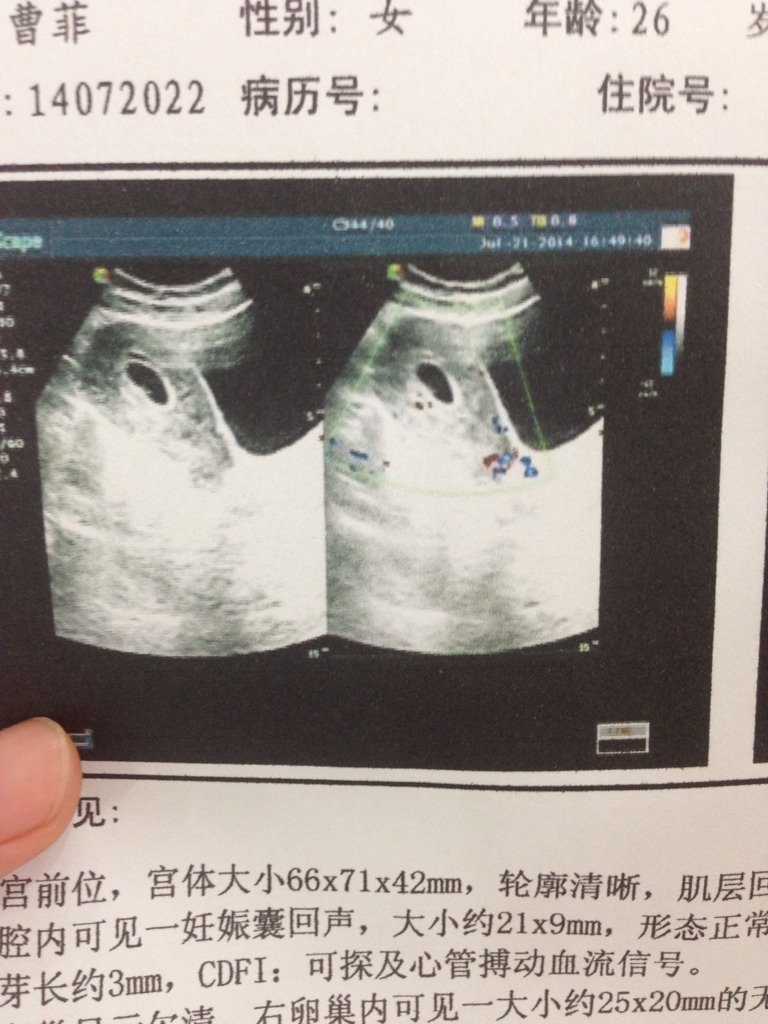

这是我怀孕六周的彩超.有宝妈们会看是男是女么?准不准? 这是我怀孕六周的彩超..有宝妈们会看是男是女么?准不准? 点击展开 喵喵喵 2014-08-08 17:49 为您推荐: 其他回答 貌似男孩 15261217923 2014-08-09 00:16 男孩在子宫后,女孩在子宫前,不过这个也不准,你可以在刚怀孕一个月的时候拿早早孕测,下面是紫色的就是男孩 若角色对调你说好不好 2014-08-08 18:09 女孩 若角色对调你说好不好 2014-08-08 17:53 不知道 茜茜麻麻 2014-08-08 17:51 相关问题 怀孕23周了,想去做个彩超,不知道费用是多少,宝妈们告诉我一下,谢谢 孕20周了,还没有做四维彩超,哪位好心的宝妈能不能把你们家照的给看下是什么样的